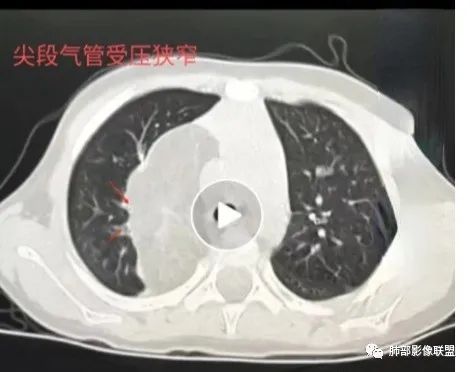

定位:肺内?尖段气管未见明显显示,腔静脉受压向右推移?病灶内可见前段动脉穿行,脂肪密度为主。

患儿3岁 咳嗽检查发现纵隔占位。右肺上叶受压表现,占位以脂肪组织密度为主,似见分隔,首先考虑为脂肪母细胞瘤,鉴别脂肪瘤,畸胎瘤。

取决于瘤体所在部位,多为无痛性肿块,局部皮温正常,表面光滑,质地软硬不一,边界较为清楚;若肿瘤位于体表,可无明显症状;若肿瘤位于纵隔,可因气管的受压而出现咳嗽和呼吸困难等症状。值得注意的是,脂肪母细胞瘤容易对重要结构和器官浸润生长,导致功能障碍甚至死亡!